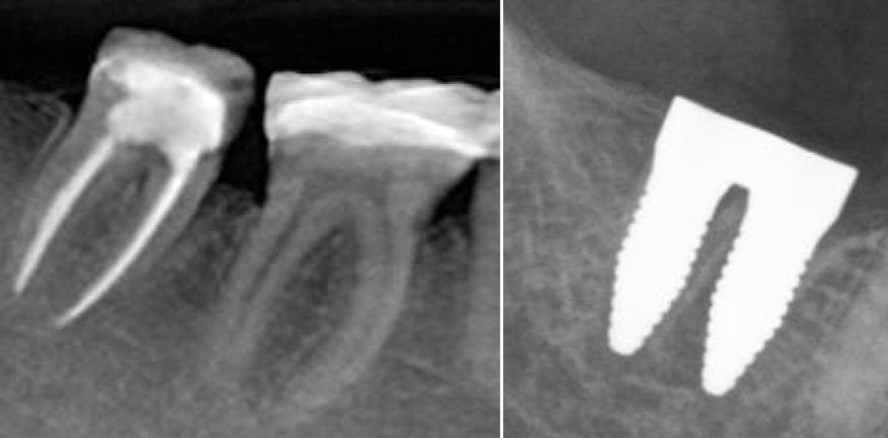

Nach Extraktion von Molaren sind zum Ersatz mit Sofortimplantaten mehrere Zahnwurzelfächer vorhanden und das interradikuläre Septum ist nicht immer zu schonen. Eine Idee zur besseren und einfacheren Stabilisierung wäre die Insertion mehrerer Implantate oder eines großvolumigeren Implantats, das die vorhandenen Zahnfächer besser ausfüllen kann, um eine bessere Primärstabilität zu erzielen (Abb. 1a und b).

Hier knüpft die innovative Idee des vom Bundesministerium für Wirtschaft und Energie (BMWi, Förderkennzeichen: KF3259802CS4) geförderten Projekts zur Entwicklung zweiwurzliger Zirkoniumdioxidimplantate zum Zweck der Sofortimplantation im Molarenbereich an. Dabei stand bei dem Projekt die Entwicklung eines Implantatkörpers im Vordergrund, der zur Hartsubstanzschonung eine natürliche Zahnwurzelgeometrie aufweist. Nebst der Implantatform soll sowohl eine hohe Primärstabilität als auch eine optimale Einheilung erreicht werden. Aufgrund der Verwendung von Zirkoniumdioxidmaterialien ist eine der natürlichen Zahnfarbe entsprechende ästhetischere Gestaltung möglich.

Das für die Implantate verwendete Zirkoniumdioxid zeigte sich in vitro insgesamt ohne Einschränkungen zytokompatibel gemäß DIN EN ISO 10993-5/-12-Normbestimmungen. Auf Basis dieser Ergebnisse wurden erste Prototypen für verschiedene Molaren hergestellt (Abb. 2a und b). Diese werden aktuell in vivo untersucht.